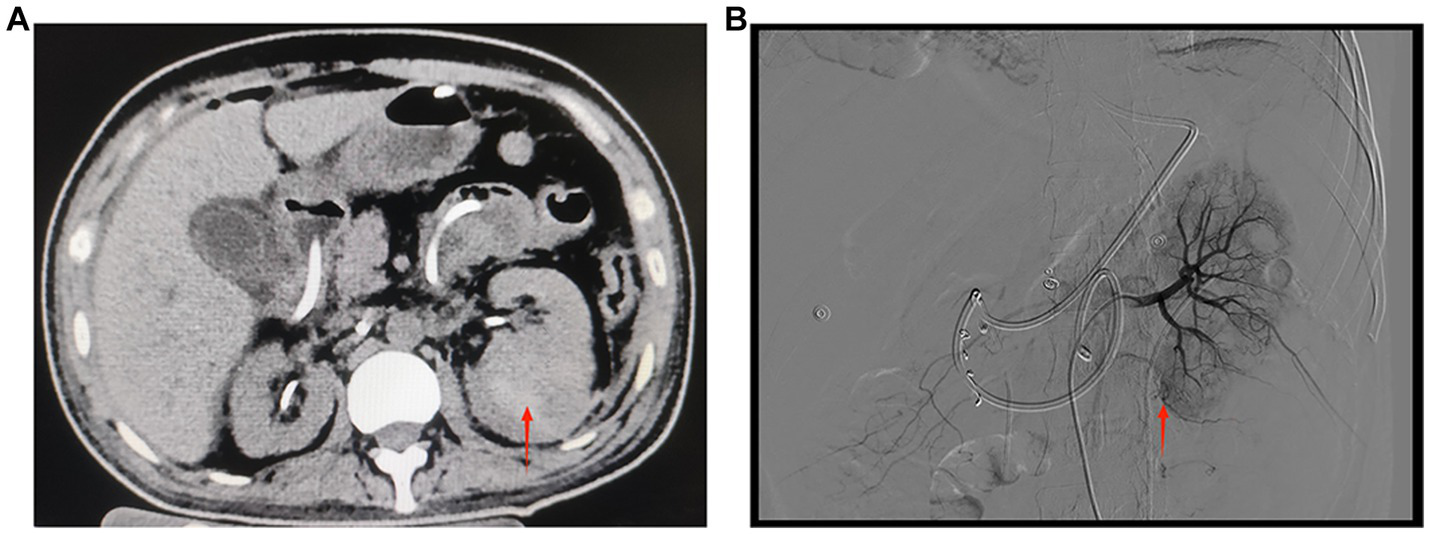

Figure 3

(A) CT of both kidneys. The left kidney is increased in size, heterogeneous in density, with multiple patchy hyperdense shadows and a few flocculent hyperdense shadows seen in the perirenal space of the left kidney. The red arrow indicates a hematoma in the lower pole of the left kidney (September 27, 2022, day 5 of transfer to ICU). (B) Digital subtraction angiography of the left renal artery. The red arrow shows suspicious active extravasation of the subsegmental artery supplying the lower pole (October 18, 2022, day 26 of transfer to ICU).